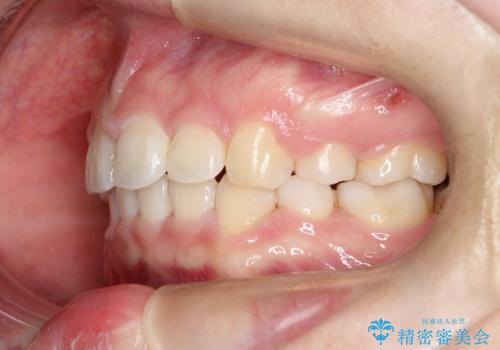

- 口元が出ていることを主訴に来院されました。

上下左右小臼歯を抜歯して審美装置で治療を行いました。

口元もスッキリと変化し、大変満足していただきました。